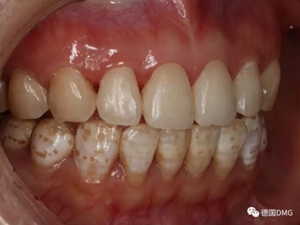

(下圖是拋光完成)

治療完成的上頜牙齒和未治療的下頜牙齒形成明顯對比。

治療前和治療后的對比,患者很高興很滿意。